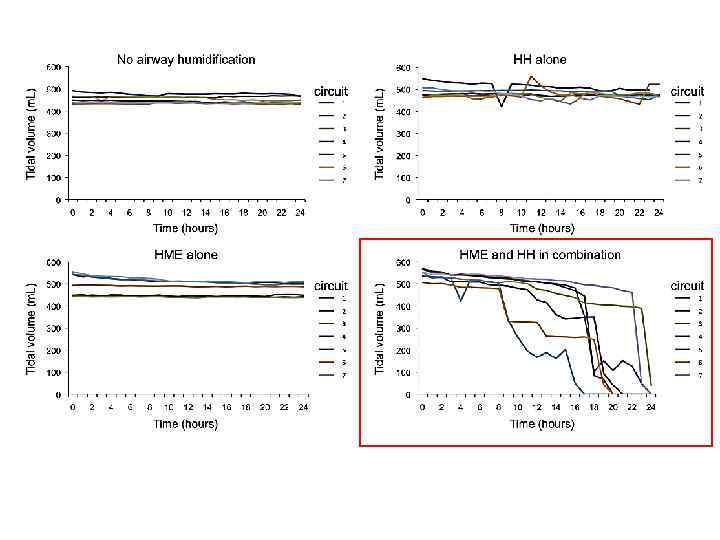

ТВО и увлажнитель

ТВО и увлажнитель